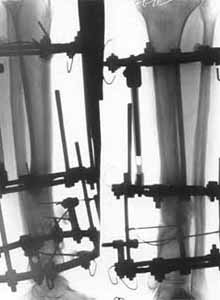

False joint of lower/third of shinbone.

Osteosynthesis with elimination of deformations and electrostimulation(period of treatment - 3 monthes). Osteosynthesis with elimination of deformations and electrostimulation(period of treatment - 3 monthes).

Osteosynthesis with elimination of deformations and electrostimulation (period of treatment - 3 monthes).